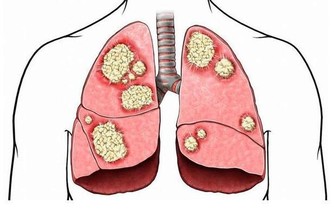

腫瘤阻塞,當腫瘤長至相當體積,或浸潤腸壁肌層時,

可引起腸管狹窄,腸腔變小,腸內容通過受阻。

當大腸腫瘤相對較大且有糜爛、潰瘍或感染時,

才可能發生大便習慣、次數的改變,以及便秘或不明原因的腹瀉。